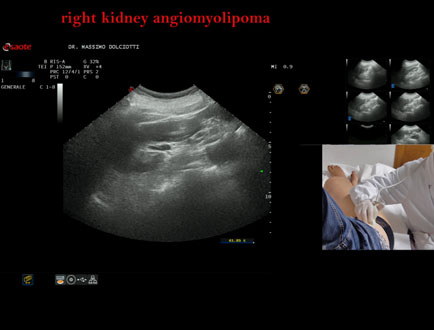

Data inserimento: 15/09/2023

Ecografia del: 06/09/2023

Strumento: Esaote MyLab Eight

Sonda: Convex Multifrequenza 1-8 MHz

Età Paziente: F 37 anni

Motivazione dell'esame: follow up per angiomiolipoma renale.

Commento all'esame: le immagini ed il video documentano la presenza di immagine iperecogena a margini definiti, in sede mesorenale cortico-midollare del rene destro, delle dimensioni di 12,1 x 9,9 mm, da ricondurre ad angiomiolipoma renale.

Conclusioni: angiomiolipoma renale destro (right kidney angiomyolipoma).

Presentazione: Dr. Massimo Dolciotti - Ancona

Elaborazione digitale: Andrea Dini - Ancona